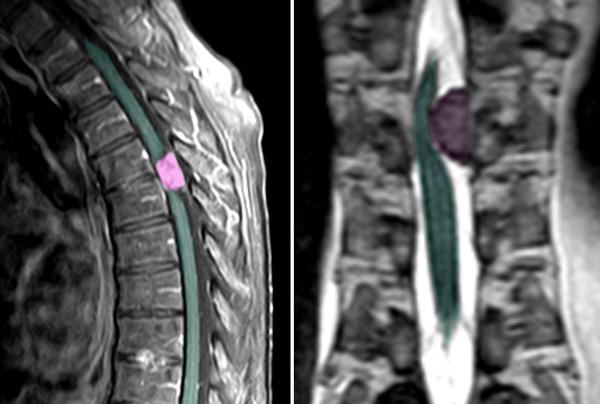

Mηνιγγίωμα θωρακικής μοίρας της σπονδυλικής στήλης με σημαντική πίεση στον νωτιαίο μυελό. |